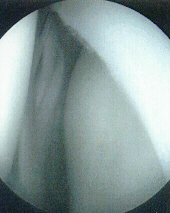

IMAGING STUDIES: An MRI of his left knee showed no evidence of cruciate

ligament injury. The lateral meniscus was not adequately visualized as

the MRI was of poor quality. Plain radiographs were not obtained.